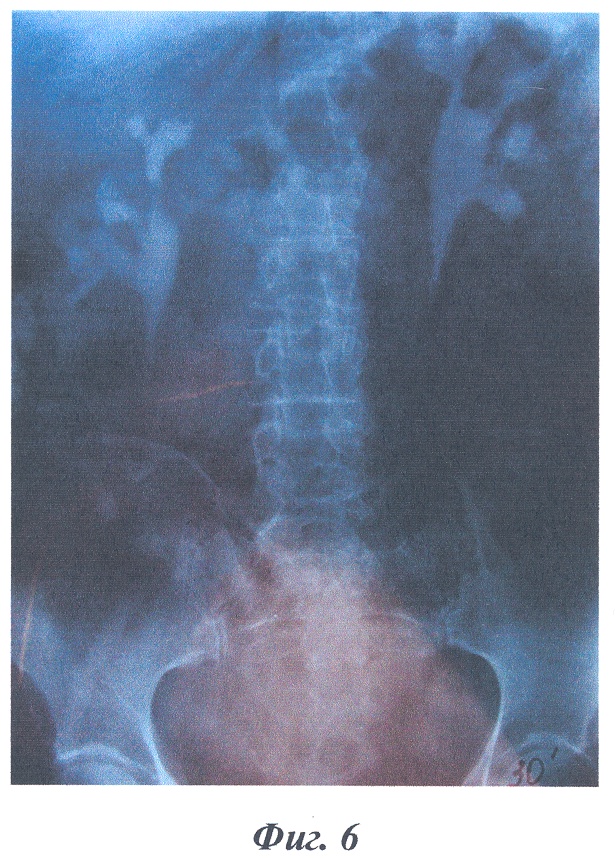

На фиг.4-6 изображены рентгенограммы клинического примера формирования накопительного мочевого резервуара предлагаемым способом.

В качестве примера приводится выписка из истории болезни больной Ж., 51 года, И.Б. №1111, которой по поводу постлучевой облитерации мочевого пузыря и уретры после лечения рака шейки матки T1N0M0 (фиг.4 – экскреторная урограмма до операции) 12.04.2004 г. была произведена операция (№169) с формированием “сухой” накопительной уростомы по предложенному способу. Послеоперационное течение гладкое, больная выписана в удовлетворительном состоянии на 29 сутки после операции.

Заключительный диагноз: постлучевая облитерация мочевого пузыря и уретры. Состояние после лечения рака шейки матки T1N0M0. Больная осмотрена через 2 года, данных за рецидив и метастазы не выявлено, при экскреторной урографии отмечается удовлетворительная функция почек, расширения чашечно-лоханочных систем и мочеточников нет (фиг.5, 6).